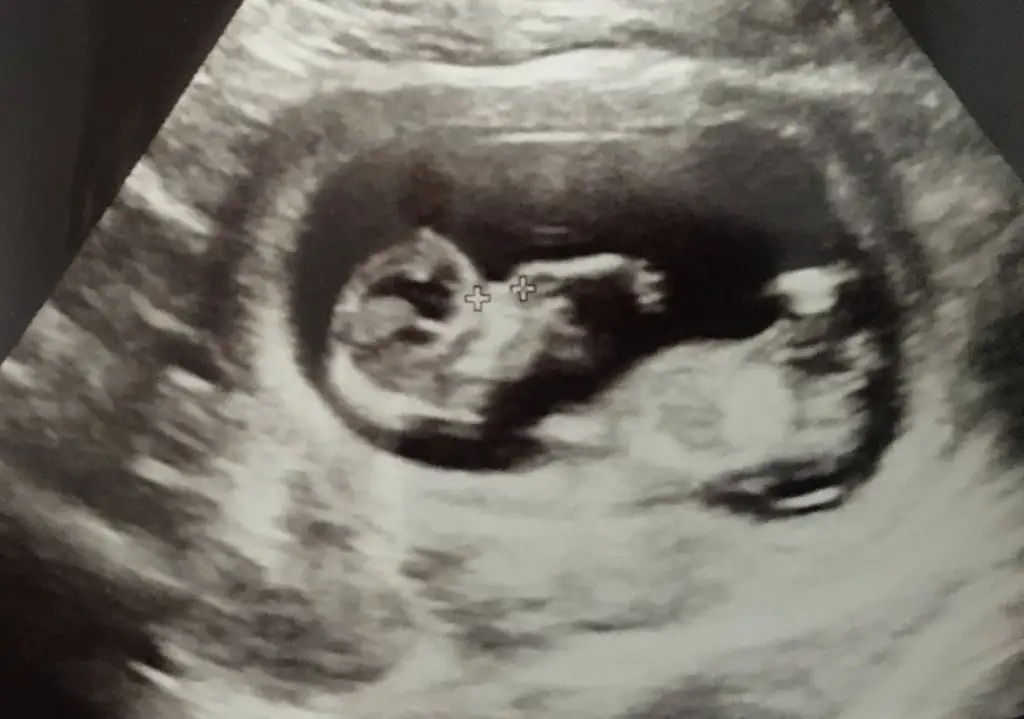

Yordum sizi🙈 hakkınızı helal edin. Ben videodan bir kaç fotoğraf daha ekledim. Tekrar bi bakabilirseniz çok sevinirim🌸🌸

12+5 tahmin edebilir misiniz ? Karından ultrason Ikra meyra Ikra meyra